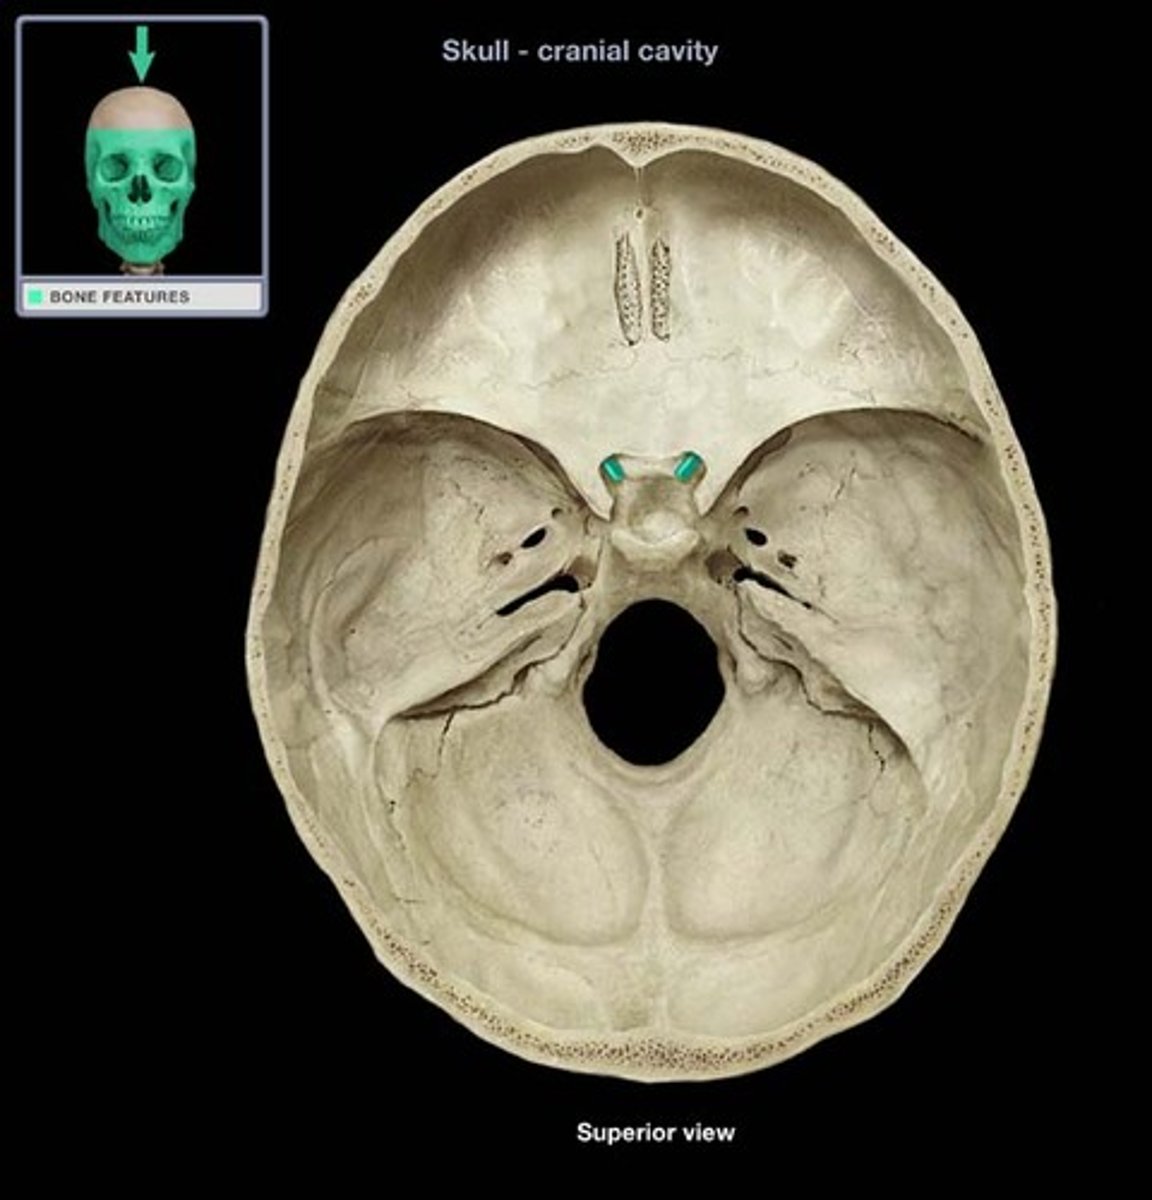

Foramen Magnum

The hole in the base of the skull through which the spinal cord passes

Hypoglossal Canal

Foramen in the occipital bone of the skull through which the hypoglossal nerve traverses

Foramen Lacerum

A triangular hole in the base of the skull located between the sphenoid, apex of petrous temporal and basilar part of occipital

Jugular Foramen

CN IX, X, XI, superior bulb of internal jugular, inferior petrosal and sigmoid sunuses, meningeal branches of ascending pharyngeal and occipital arteries pass through

Occipital Condyles

Rounded projections lateral to the foramen magnum that articulate with the first cervical vertebra (atlas)

Optic Canal

A cylindrical canal running obliquely through the lesser wing of sphenoid bone near the base where it joins the body of sphenoid. It transmits the optic nerve and ophthalmic artery.

Foramen Rotundum

Located at the base of the greater wing of the sphenoid, inferior to the superior orbital fissure. It provides a connection between the middle cranial fossa and the pterygopalatine fossa. The maxillary nerve (branch of the trigeminal nerve, CN V) passes through this foramen.

Foramen Spinosum

The middle meningeal artery, middle meningeal vein, and the meningeal branch of the mandibular nerve pass through the foramen.

Foramen Ovale

An oval shaped opening in the middle cranial fossa located at the posterior base of the greater wing of the sphenoid bone. It transmits the mandibular division of the trigeminal nerve (CN V3) and the accessory meningeal artery.

Sella Turcica

Depression in the sphenoid bone where the pituitary gland is located

Cribriform Plate

Superior surface of the ethmoid; perforated by a foramina which allows passage of the olfactory nerves, which provide sense of smell

Crista Galli

A thick, midline, smooth triangular process arising from the superior surface of the ethmoid bone, projecting into the anterior cranial fossa. Attaches to fall cerebri.